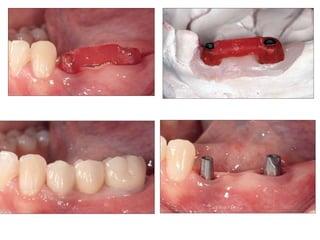

Implants require more precise impressions than crowns and bridges because implants lack a periodontal ligament to compensate for inaccuracies. It is critical to accurately record the three-dimensional position, angulation, and depth of implants to obtain a proper fitting definitive restoration. Making high quality impressions at the implant or abutment level is necessary to successfully fabricate implant prostheses.